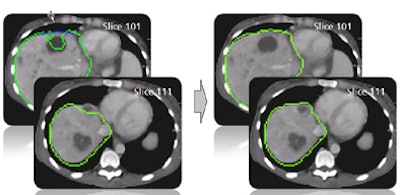

| In step two, morphological postprocessing ensures a coherent, smooth mass. The opening process removes small artifacts, connected component analysis removes separated parts, and closing eliminates small gaps. |

| The results demonstrate correction of the segmentation in 3D in the user-selected 2D slice, as well as automatic correction in the adjacent slices. |